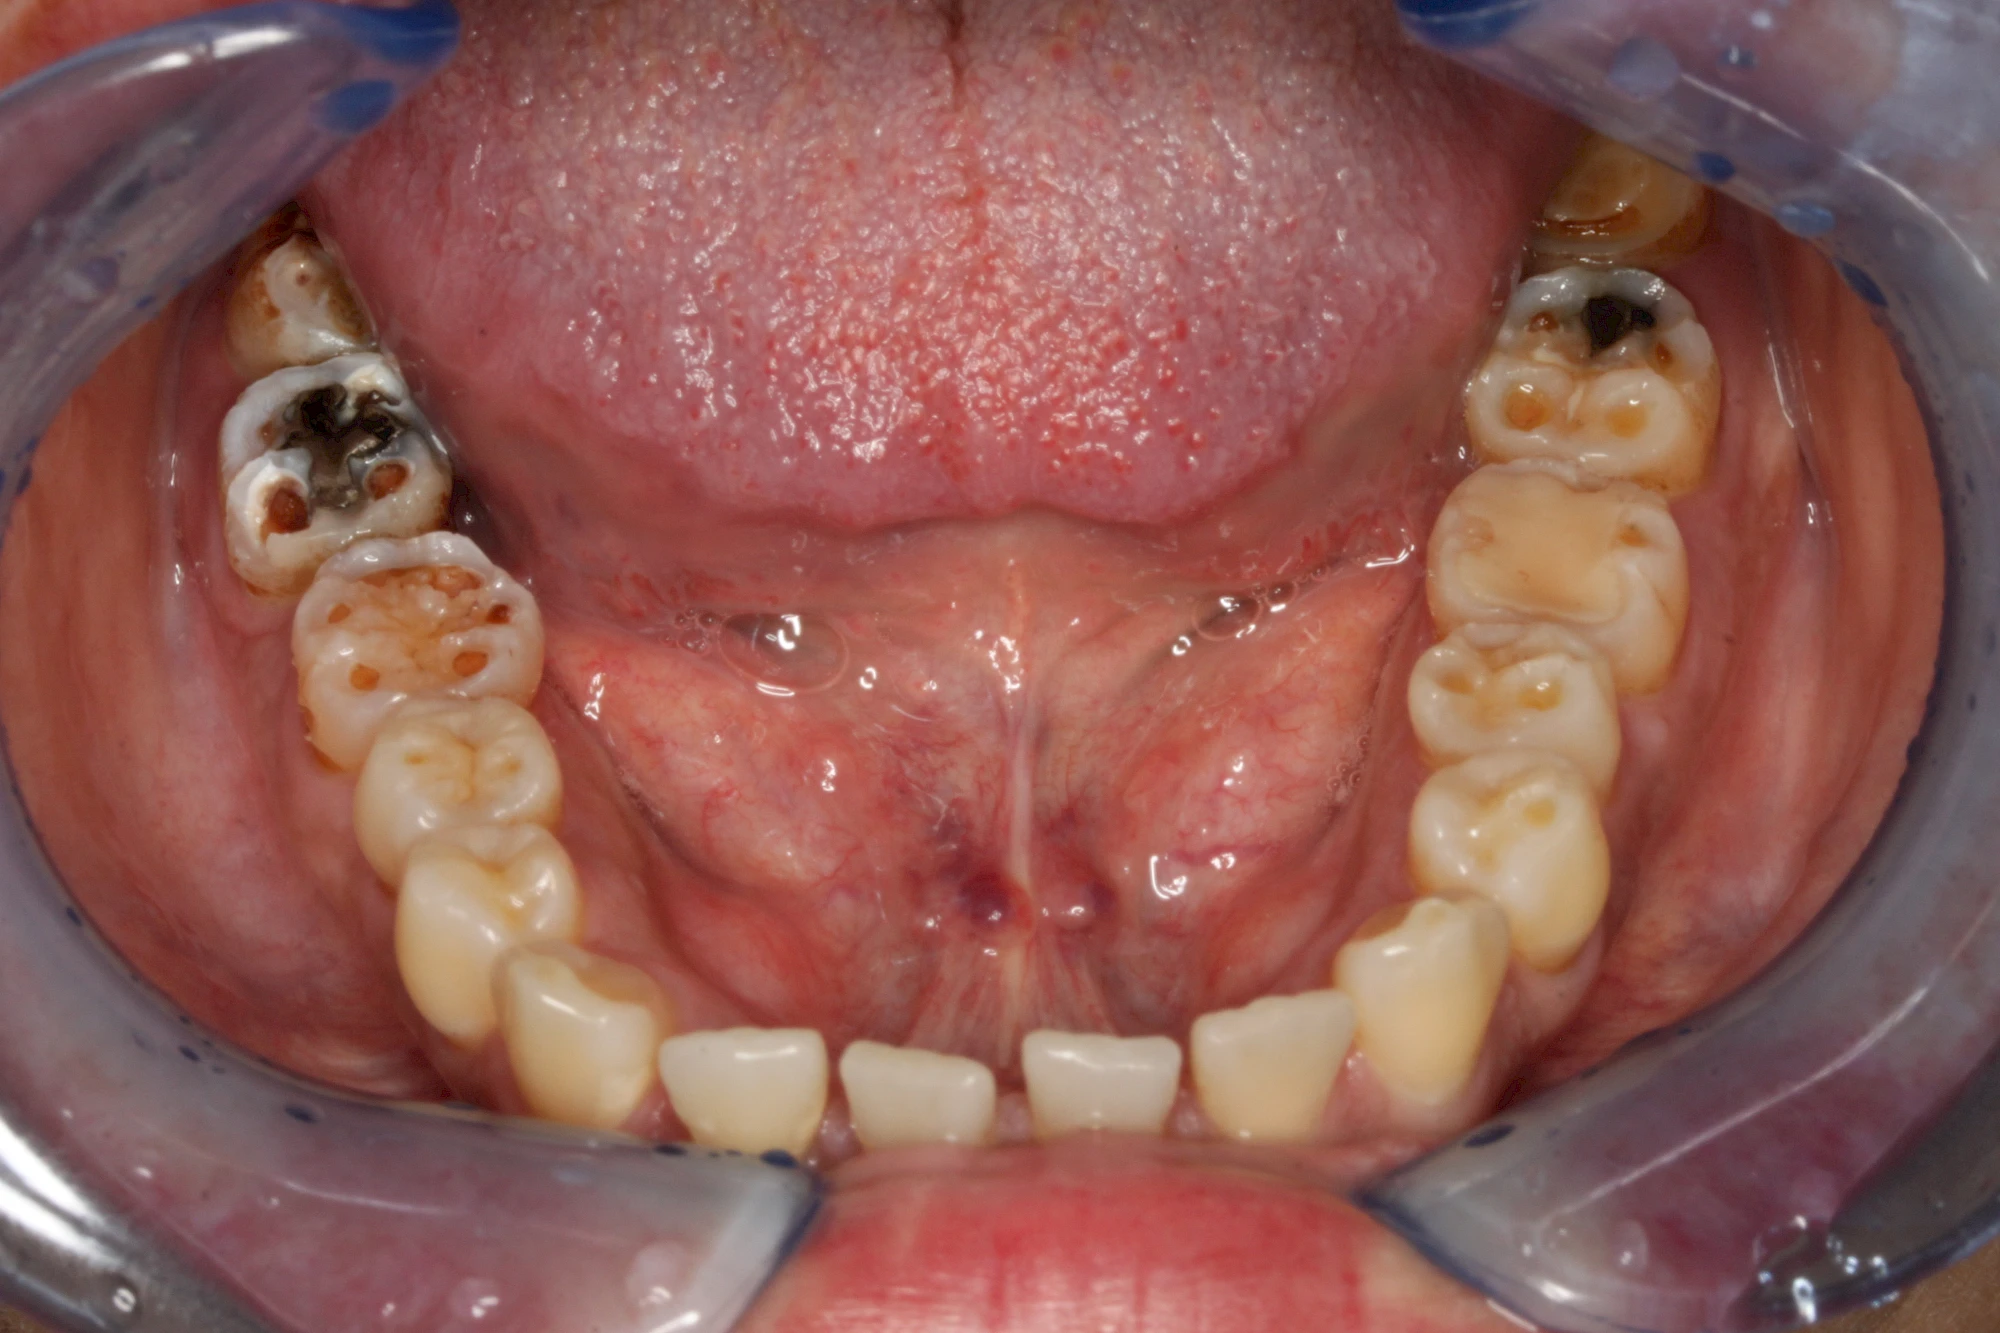

Auswaschung (Erosion) dagegen ist eine Verschleißerscheinung der Zähne aufgrund von immer wiederkehrenden Säureangriffen durch die Nahrung, verstärkt zum Beispiel durch den Genuss säurehaltiger Getränke oder Speisen. Auch bei Menschen mit einer Essstörung (z. B. Bulimie) können die Zähne durch die Magensäure ausgewaschen erscheinen.